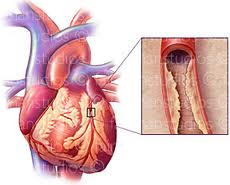

علل سکته قلبی

سکته قلبی معمولا وقتی اتفاق میافتد كه لخته خونی در مسیر جریان خون عروق كرونری ـ كه تغذیهكننده عضله قلبی…

مهمترین علت سکته قلبی

میزان مرگ و میر ناشی از بیماریهای قلبی 25 % و مرگ و میر ناشی از سکته مغزی در حدود…

علت بروز سکته قلبی

سکته به معنی حادثه است. سکته قلبی به معنی حمله قلبی و علتش بسته شدن و انسداد رگهای خون دهنده قلب…